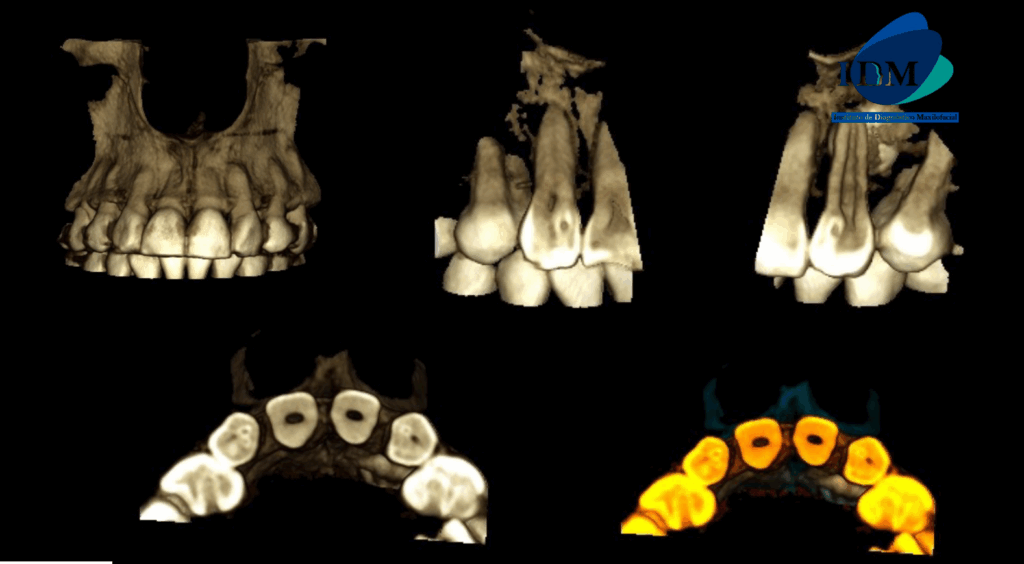

A la evaluación de la tomografía de campo mediano en cortes axiales, transaxiales y tangenciales se evidencia un detalle que en la panorámica paso un poco inadvertida y es que las piezas 12 y 22 presentan una alteración de la morfología coronaria compatible con dientes invaginados.

RECONSTRUCCIÓN 3D